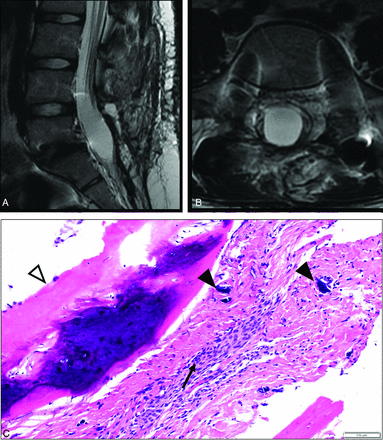

A 16-year-old female patient with a history of remote tethered cord release and posterolateral fusion. MR imaging T2-weighted images in the sagittal (A) and axial (B) planes demonstrate low signal thickening of the thecal sac with peripheralization and clumping of the nerve roots. C, H&E stains of the resection specimen from the thecal sac at the lumbar spine demonstrate meningothelial cells within the resected leptomeninges (black arrow), with ossification along the margin of the specimen (white arrowhead) as well as scattered foci of calcification (black arrowheads), consistent with AO.